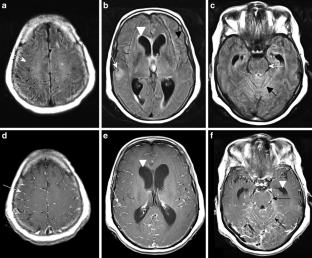

The CNS TB can be manifested (1) diffuse as tuberculous meningitis (TBM), (2) localized as tuberculoma or (3) tuberculous abscess or (4) in extradural and intradural spinal infections. Information on clinical presentation, underlying pathology and the distinguishing features is demonstrated. The TBM is further described, which may lead to cranial nerve palsy, hydrocephalus and infarction due to associated arteritis of the basal perforators. The differential diagnoses are vast and include other infections, such as bacterial, viral or fungal meningoencephalitis, malignant causes or systemic inflammation with CNS. Complicating factors of diagnosis and treatment are HIV coinfection, multi-drug resistance and TB-associated immune reconstitution inflammatory syndrome (IRIS).